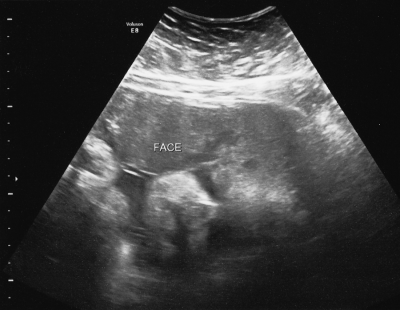

How far along: 36 weeks! (The extreme close-up of baby’s face was from a non-stress test I had at 35 weeks)